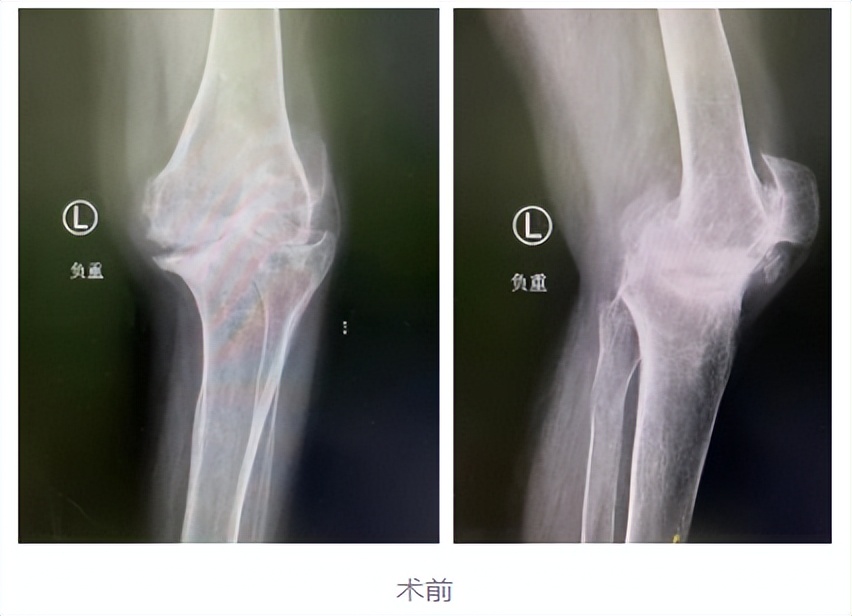

为求进一步治疗,李大姐在家人的陪伴下来到我院关节外科,经过相关系统检查后,确诊为类风湿性关节炎及双膝骨性关节病(KL分级 IV级)。

20年前,李大姐双膝关节出现疼痛症状,尤其是在劳累后这种疼痛感更重,当时在当地医院被诊为类风湿性关节炎,之后的时间里她一直以药物控制。但在10年前,李大姐双膝关节疼痛等症状明显加重,每天早晨还会有双膝僵硬的情况,尤其是左膝,在行走或其他活动时受限明显,严重影响日常生活。